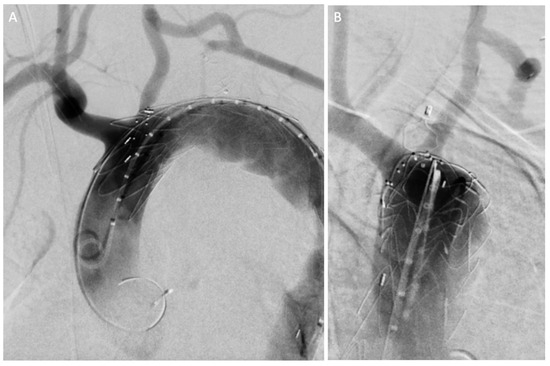

| Current Case-1 | 48 | M | Aortic arch | Cough | 25 years | Hybrid (ET + TEVAR) |